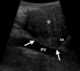

Superior mesenteric artery (SMA) syndrome is a gastro-vascular disorder in which the third and final portion of the duodenum is compressed between the abdominal aorta (AA) and the overlying superior mesenteric artery. This rare, potentially life-threatening syndrome is typically caused by an angle of 6°–25° between the AA and the SMA, in comparison to the normal range of 38°–56°, due to a lack of retroperitoneal and visceral fat (mesenteric fat). [Source: Wikipedia ]